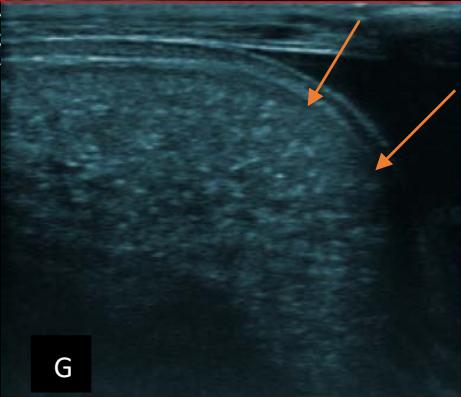

Figure 5: Abdominopelvic ultrasound control after 6 courses of chemotherapy in the same 3 year old patient with a ruptured left renal nephroblastoma; Images A, F, G, and H: show regression of the solid, endo and exo renal, left nephroblastoma mass treated with 6 courses of chemotherapy (current volume 430 ml vs) Images: B, C, and: show persistence of thrombotic permeation pan vena cava and ipsilateral renal. Image E: shows a volumetric regression of the intra-lesional hematic collection, at the tumor rupture estimated at 34.49 ml VS, Image I: represents the right kidney in B mode which is of normal echoculture. Source: Dr. Frederick Tshibasu Tshienda database.

Figure 6: 9-year-old sickle cell patient, referred for abdominal bloating with significant collateral venous circulation, in whom we noted: Image A: mass, Image B: healthy renal stump, inferior polar; Image C: left transmedian extension, Image D: thrombosis of the vena cava segments: supra, retro and sub hepatic, sparing a part of the supra hepatic vena cava segment over $30~\mathrm{mm}$. Image: Ascites of great abundance, Image F: normal left kidney, Image G: splenic microcalcifications, Image H: celiac adenopathy, Image I: sub pleural pulmonary nodules with the biggest measuring $3.88 \times 3.81 \mathrm{~mm}$, Image j: left pleurisy of great abundance. Source: Dr. Frederick Tshibasu Tshienda database.